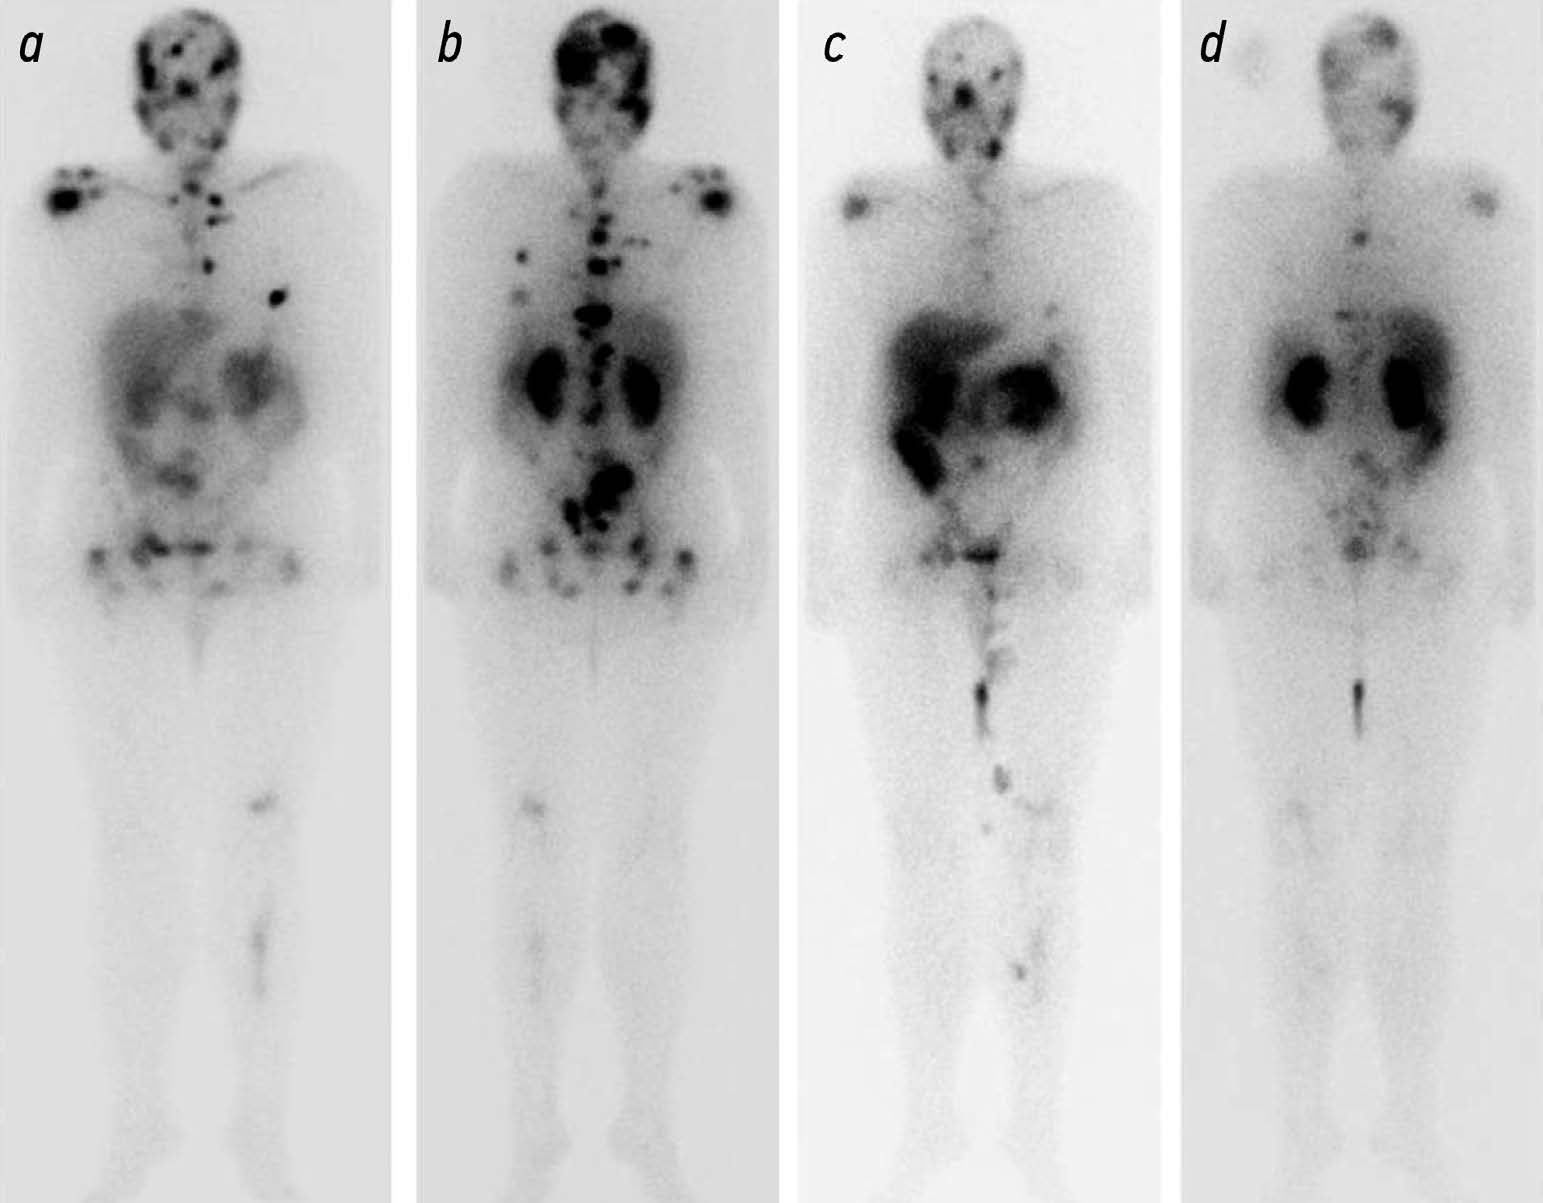

Potential use of radiation methods for diagnosing bone metastases of castration-resistant prostate cancer: a literature review

Abstract

Metastatic castration resistant prostate cancer (mCRPC) is the tumor progression with the development of resistance to androgen deprivation therapy. The incidence of bone metastases in these patients reaches 90%. Radiology is widely used to diagnose mCRPC. Computed tomography (CT) and magnetic resonance imaging (MRI) are beneficial in anatomic imaging, but have some limitations in evaluating effectiveness of disease treatment. Scintigraphy is used to screen for bone metastases, but is poorly suited for assessing disease progression. Positron emission tomography (PET) combined with CT and single photon emission CT are used for early detection of local or systemic spread of prostate cancer. PET of prostate specific membrane antigen is used to predict the effectiveness of anti tumor therapy based on the absorbed dose of a radiopharmaceutical (RP). The introduction of RPs (177Lu-PSMA) opens up new perspectives for radionuclide therapy with simultaneous evaluation of its efficacy using hybrid visualization. The potential use of radiology in the diagnosis of bone metastases is of particular interest for the analysis and systematization of the data obtained and for the development of indications for radioligand therapy and the evaluation of its efficacy.

Published data indicate that radiologic modalities for the diagnosis of mCRPC vary in sensitivity and specificity and have their own advantages and limitations, so these modalities should be combined.

The development and improvement of methods to quantitatively assess treatment efficacy and identify prognostic markers will enable more informed selection of treatment strategies and radiopharmaceuticals, leading to improved overall survival.